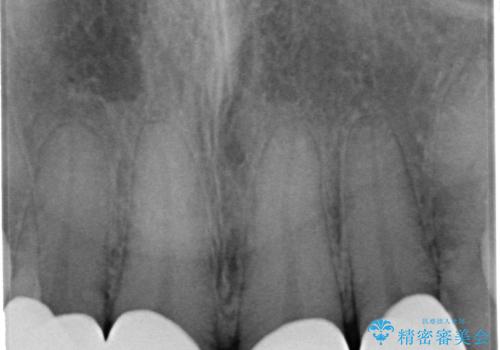

前歯の劣化したコンポジットレジン修復をセラミッククラウンへ

自然な歯の仕上がりに満足いただくことができました。

- 52.8万円(ジルコニアクラウン×4・仮歯×4)費用は治療当時の料金となります